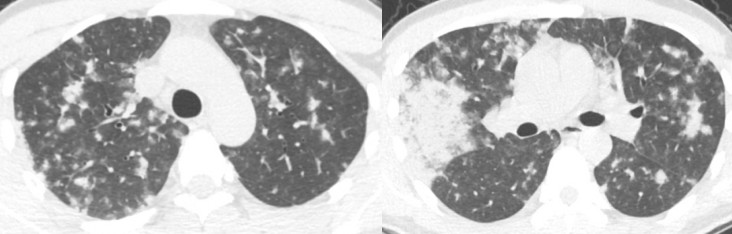

男性,85岁,发热、气短。1月17号表现为两肺斑片状实变影,经过一轮治疗,效果欠佳,病情继续进展,两肺比较对称,没有心衰,也没有水肿的改变。最终诊断是重症肺炎,调整碳青霉烯类药物的治疗后有所好转。

病例1:继发性肺结核

两肺病变,但是以右肺为主,总体的病变都在中上肺。

病例3:肺腺癌

这个病人表现为两肺多灶、多斑片的实变,在右中下叶肺可以看到实变,仔细看两肺还有一些小点状。CT表现为右上叶明显实变,实变外周有小结节影,更低的层面可以看到右中叶明显实变影,另有磨玻璃影,右下叶有些实变影以及小叶中心的结节。在对侧,主要更多的是一些细小的点状。这个病人低烧,刚开始会想到炎症,但是这个病人不是常见的炎症表现,第一是因为边界比较清楚,第二是由于外周伴有小结节,所以这时就要小心,说明这个病变不是急性,要想到炎症之外的病变。这个病人最后诊断为肺腺癌。

病例1:重症肺炎

男,28岁,发热一周,咳嗽气短2天。虽然很年轻,但是住院时的病情很严重。虽然右上肺有斑片实变影,但两肺有广泛不规则的结节。CT显示的大多数边界不清晰,边缘有些类似磨玻璃影,右上叶可以看到磨玻璃样改变。这是不规则结节,不像肿瘤性病变呈边界比较清楚、比较圆的结节。这个病人的诊断是重症肺炎,调整治疗后效果很好。

病例2:曲霉菌感染

血液病病人,治疗后发烧。两肺多发结节,大的团块可以看到充气支气管征,实际上这是一个实变影,有大肿块和小结节。血液病的病人治疗后,如果出现这样的结节,首先想到真菌感染。这个病人最后诊断是曲霉菌感染。

病例3:GPA(肉芽肿性多血管炎)

这是一个发烧的病人。CT显示左肺尖有肿块,右肺尖有结节,在膈角区可以看到团块影,右下叶在膈肌下面可以看到结节影。在右肺门也可以看见这种改变,实变边界比较清楚,中间可以看到充气支气管征。像这种不是都是一个肿块,因为肿块主要是一种占位性病变,支气管应该变细或者消失。所以出现这种病变应该想到有肺泡填充性的病变,病人发烧,除了考虑感染外,还要想到非感染。这个病人最终诊断的是GPA。

病例1:PCP

这是一个47岁男性患者,发烧。X线胸片显示两上肺有些实变,仔细看在肺门周围有淡淡的密度增高。CT显示上肺实变影,在肺门周围及更低的层面都可以看到磨玻璃影,下肺相对较少,两肺病变以磨玻璃影为主。如果发烧的病人出现这种改变首先考虑病毒性肺炎和PCP,但病毒性肺炎往往在下肺多一些。所以对于这个病人而言,放射科怀疑PCP并提醒临床检查HIV,结果为HIV阳性,后来诊断为卡氏肺孢子虫肺炎。

病例2:吸入性肺炎

这是一个89岁的老年男性,低烧。胸片显示淡淡的密度增高阴影,但CT很明确的显示为两肺磨玻璃影,在两下叶肺门后区域,中叶比较贴近叶间裂的位置。对于这样的位置,考虑吸入性肺炎,但是肺水肿也可以表现为两肺密度增高、磨玻璃影,通过追问病史发现病人因为喝水呛到了,所以诊断就比较简单。

病例3:弥漫性肺泡出血

女性,45岁,胸闷咳血。影像学表现比较典型,两肺磨玻璃影,外周无小叶间隔增厚,另外未见胸水。